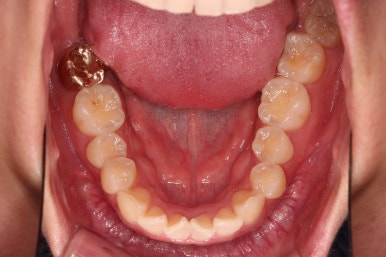

1. 초진

초진 시 입안의 모습입니다.

어금니 쪽은 약간 삐뚤긴 하지만 꼭 교정해야 할 정도는 아니고, 불편감 없이 비교적 잘 맞물리는 상태였습니다.

다만, 앞니ㅉㄱ이 공간이 부족해서 중간 치아들이 많이 회전되어있는데, 이를 환자분들의 표현에 따르면 "나비치아" 라고 부릅니다.

위아래 중간 앞니가 모두 나비치아처럼 되어있고요.

윗니가 아랫니보다 앞쪽으로 나와 있는 모습에 아래앞니가 윗니쪽으로 깊숙이 올라간 "과개교합" 양상을 보였습니다.

아래 앞니는 브라켓보다는 훨씬 작은 미니튜브 장치를 사용했습니다.

과개교합의 경우 브라켓을 부착하게 되면 씹히게 되어 치료과정이 수월하지 못하기 때문이죠.